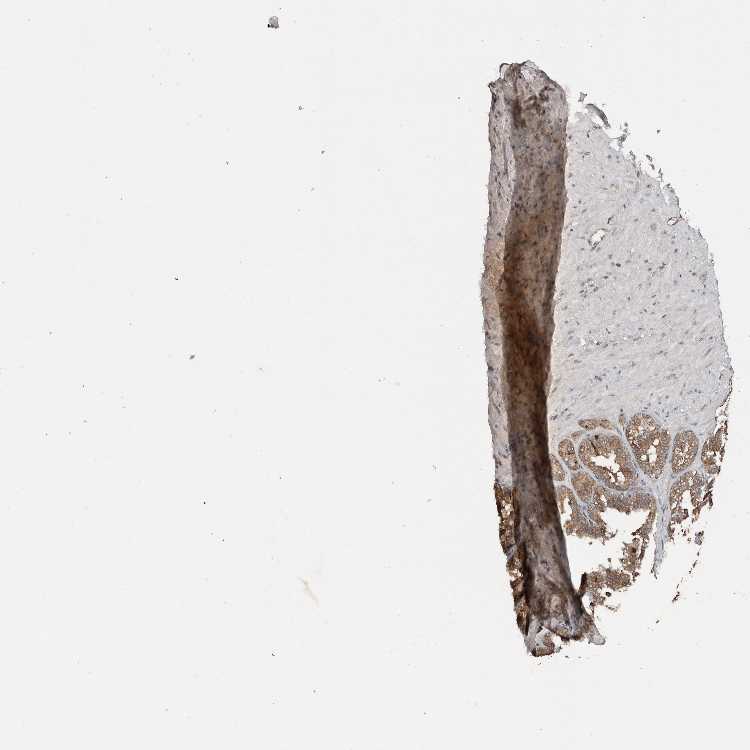

TISSUE PRIMARY DATA SEMINAL VESICLE Show tissue menu

SEMINAL VESICLE - Antibody stainingi

Antibody staining in the annotated cell types in the current human tissue is reported as not detected, low, medium, or high, based on conventional immunohistochemistry profiling in selected tissues. This score is based on the combination of the staining intensity and fraction of stained cells.

Each image is clickable and will lead to virtual microscopy that enables deeper exploration of all samples and also displays staining intensity scores, fraction scores and subcellular localization as well as patient and tissue information for each sample.

Antibody HPA024069Antibody CAB026151

Glandular cells MediumLow